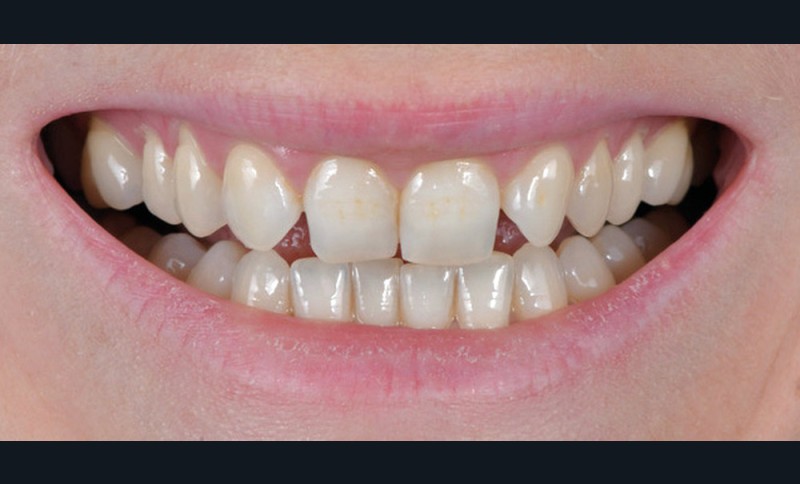

Le Pr Olivier Sorel insistera sur l’importance du respect des formes et des proportions anatomiques, pour éviter de voir apparaître, notamment chez les adultes, de très inesthétiques triangles noirs lors de la phase d’alignement (fig. 6a-b). Il présentera sa démarche diagnostique (évaluation de la forme des dents et de la dysharmonie dento-dentaire, fig. 7a-c) et l’intégration de la réduction amélaire proximale au plan de traitement, afin de s’assurer, en fin de traitement, la présence de papilles gingivales et donc d’un sourire harmonieux (fig. 8a-d).

Les Drs Marie Clément et Clara Marcoux aborderont ensuite les différents apports de la dentisterie esthétique aux traitements orthodontiques. Les problèmes de dyschromies isolées ou généralisées, congénitales ou acquises seront développés ainsi que les anomalies de proportions dentaires (dents riziformes…), le maquillage (transformation d’une canine en incisive latérale…) et le remplacement des dents antérieures. Les auteurs présenteront l’intérêt du Digital Smile Design dans le diagnostic et la communication et l’arsenal thérapeutique à notre disposition pour améliorer la satisfaction de nos patients (éclaircissement, traitement des taches de l’émail, composites stratifiés, fig. 9a-d).